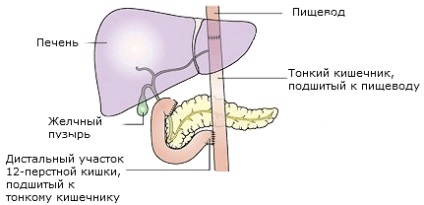

Diagrama arată conexiunea esofagului, duoden 12 a intestinului subțire și după operația suprapuse anastomoză în formă de Y Roux

În cazul în care tumora este situat în apropiere de locul trecerii de esofag, în stomac, este adesea îndepărtat și o parte din esofag. Această operație se numește ezofagogastrektomiya. Esofagul superior combinat (ligat) la nivelul intestinului subțire.

Diagrama arată conexiunea esofagului, duoden 12 a intestinului subțire și după operația suprapuse anastomoză în formă de Y Roux